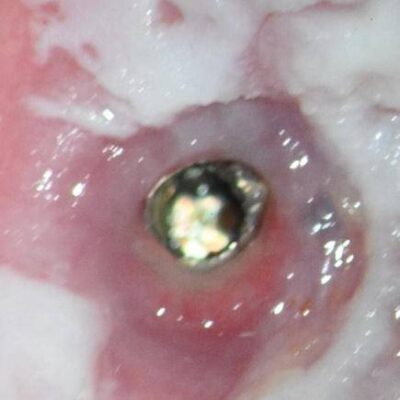

The patient presented on referral for retrieval of a fractured abutment and abutment screw from a BlueSkyBio 4.3 Max implant in the #30 site. The implant was placed on 02.12.2019 and restored on 06.24.2020. The fracture occurred in March of 2023. The case was restored with a Sirona TiBase abutment and a Cerec Emax crown. When the patient recently presented with the fractured abutment the referring Dr. could not retrieve either the retained abutment fragment or screw, so the patient was referred to our practice. When a case presents with both a fractured abutment and abutment screw it is generally easier to recover the abutment fragment first and then the screw as there is better access for the screw retrieval. With an open through bore that is the case here, so the abutment fragment was retrieved with a modified “easy-out” type screw extractor. Next, the screw fragment was evaluated and found to be mobile and residing slightly above the first implant thread, so it was a Type I case in my screw recovery algorithm. Under microscope guidance, the screw fragment was delivered with just an endodontic explorer and a modified endodontic spoon. The implant was cleaned and examined to be free of visual defects at the 25x level of visual inspection. The patient was dismissed to return to the referring doctor for restoration of the case. Prior to leaving a discussion was entertained regarding abutment types and the suggestion was made to consider avoiding another TiBase designed abutment and instead opting for a Custom Base abutment which will have a more robust titanium cross section above the implant top.